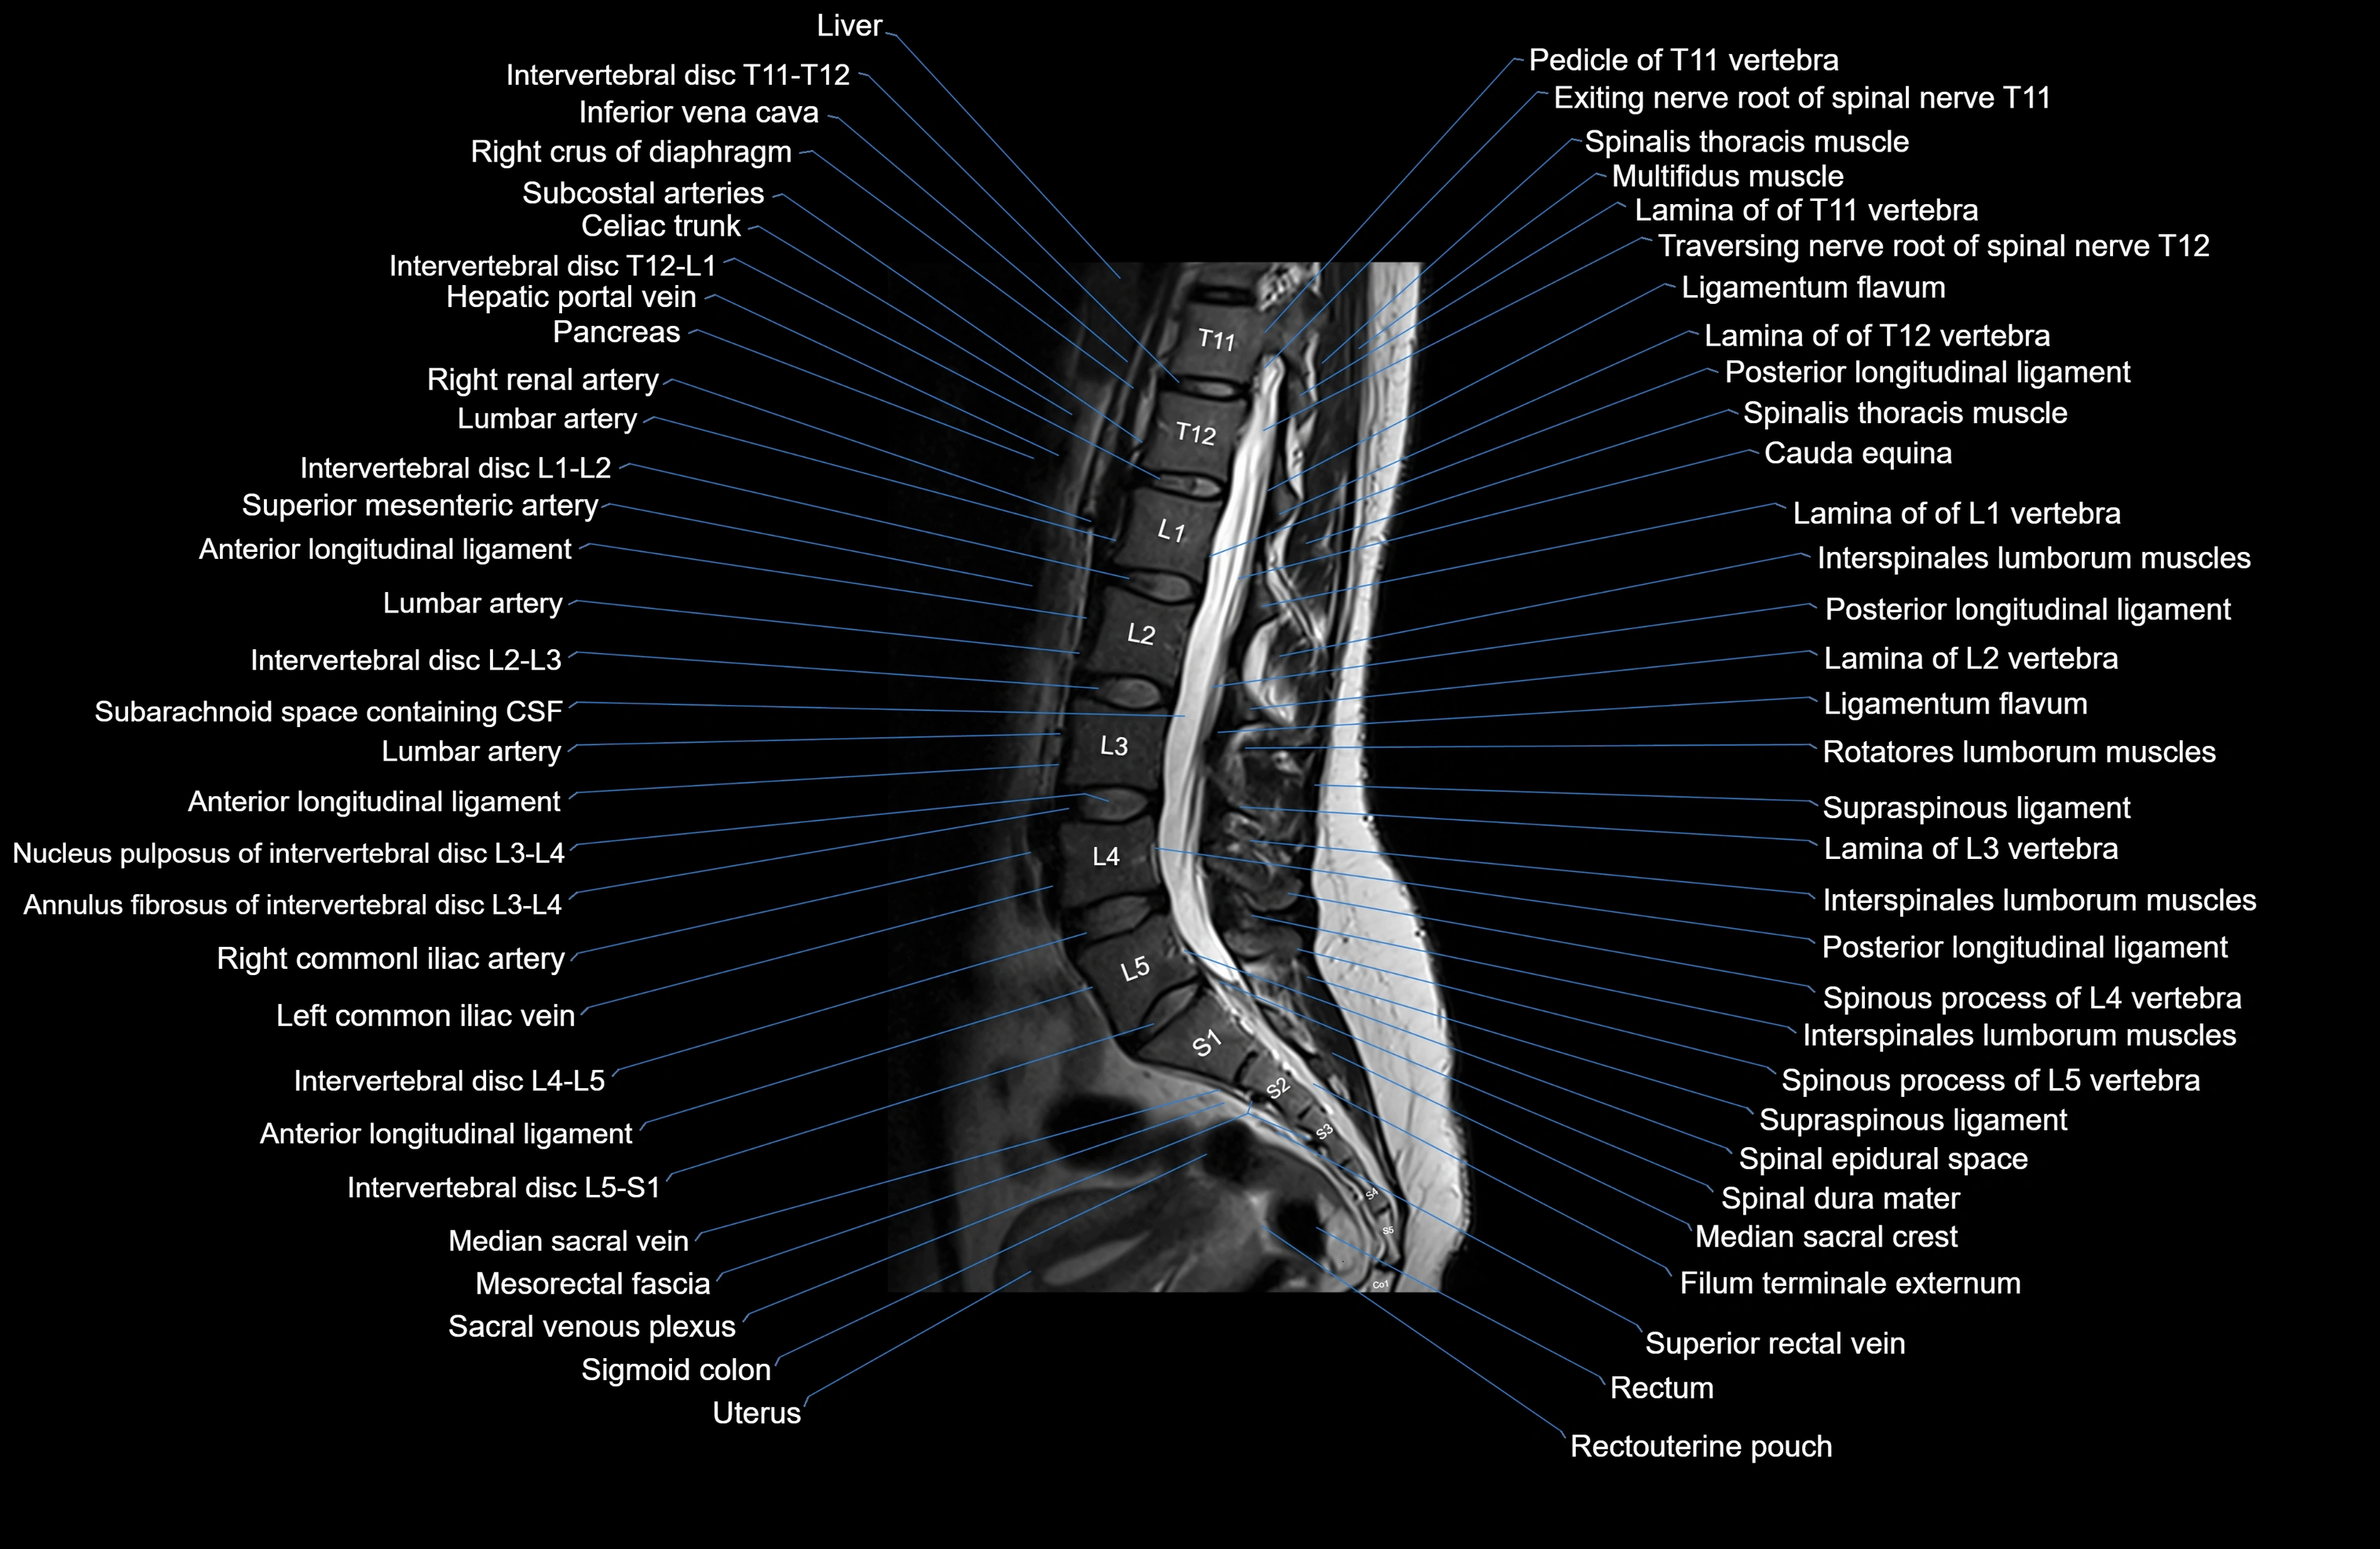

MRI images